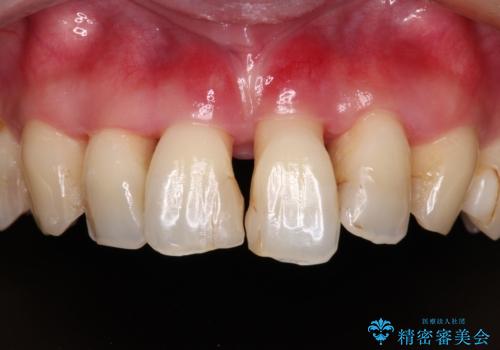

検査を行ったところ、歯周外科処置や抜歯が必要と思われる箇所が散見されたため、あらためて当院に歯周病の初期治療から行うこととしました。

自他共に認める、非常に色白の患者様であったため、黄ばんだ歯の色を白くすることを希望されており、歯周病治療の該当部位に限らず、全顎的にオールセラミッククラウンにて補綴治療を行うこととしました。

多くの外科処置を行ったため、治療期間も長くなり、患者様の負担は非常に大きなものとなりましたが、明るく健康的な口元となり、患者様には大変満足していただけました。